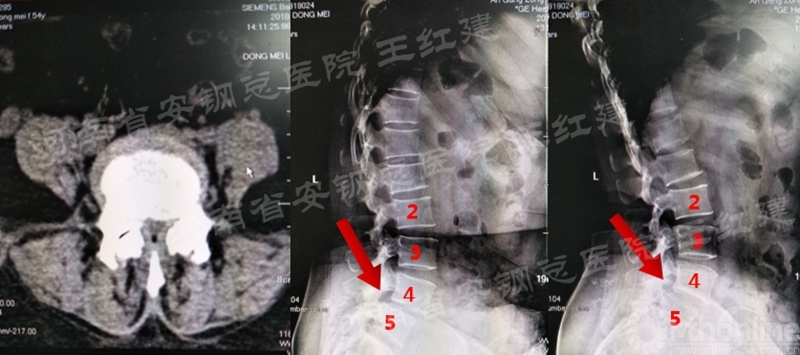

术前

术后

置入内镜通道,用磨钻和枪钳切除上位椎板下缘、下位椎板上缘及突间关节内缘,切除黄韧带,完成单侧入路双侧减压。